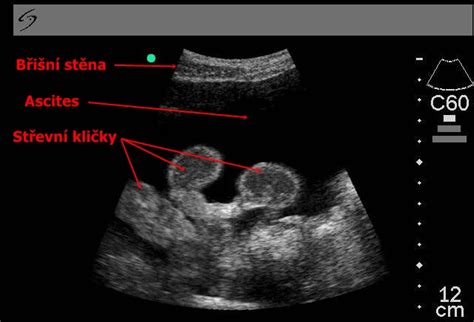

Pri diagnostike zväčšeného brucha našich mačacích pacientov zohľadňujeme rýchlosť rastu obvodu, charakteristiky dýchania a reakciu na palpáciu. Plynatosť spôsobená potravou či stavom tráviaceho systému vyvoláva tympanický zvuk pri poklepaní. Obezita je charakterizovaná pomalým a rovnomerným ukladaním tuku v tkanivách. Obvod brucha postupuje v raste stabilne a bez prudkého nárastu. Keď zvažujeme možnosť gravidity, pozornosť venujeme postupnému zväčšovaniu brucha a zmenám v správaní mačky. V neskorších štádiách možno cítiť plody. Veľké brušné nádory alebo zväčšenie orgánov, ako je zväčšená slezina či pečeň, môžu mať podobné príznaky ako ascit. Ultrazvukové vyšetrenie nám umožní rozlíšiť medzi pevnou tkanivovou hmotou a kvapalnou efúziou. Pri ťažkostiach s dýchaním musíme rozlišovať medzi pleurálnym výpotkom a ascitom. Tekutina v hrudnej oblasti vedie k výraznému dýchavičnosti bez nutnosti masívneho zväčšenia brucha. Abdominocentéza a ultrazvukové vyšetrenie (USG) prinášajú definitívnu diagnózu. Analyzujeme získanú tekutinu, aby sme určili, či je to transudát, modifikovaný transudát alebo exudát.

Diagnostika zahŕňa klinické vyšetrenie, ultrazvuk brucha, röntgen a často aj echokardiografiu. Naše prvé kroky po príchode na kliniku zahŕňajú rýchle zhodnotenie dôležitých životných funkcií. Sledujeme dýchanie, perfúziu a srdcovú frekvenciu. Potom nasleduje detailná palpácia brucha a prípadne balotovací test. Ultrazvuk brucha mačky je kľúčovým nástrojom v diagnostike. Potvrdzuje prítomnosť tekutiny a poskytuje náhľad na štruktúry pečene, sleziny, obličiek a čriev. Táto metóda tiež umožňuje bezpečné usmernenie ihly pri abdominocentéze. Ďalej sa zameriavame na krvné testy mačky. Vykonávame kompletný krvný obraz a biochemický profil, z ktorého zahrňuje hodnotenie navyše ALT, AST, ALP, bilirubínu, albumínu, urey, kreatinínu a elektrolytov. Pri podozrení na dysfunkciu zrážania krvi meriame PT a aPTT a u starších mačiek taktiež T4. Prostredníctvom abdominocentézy získame tekutinu pre cielenú analýzu. Táto analýza ascitovej tekutiny obnáša cytológiu, kvantifikáciu bielkovín, počet buniek a albumínový gradient. Porovnávame kreatinín a draslík v ascitickej tekutine so sérom pri podozrení na uroabdomen. Pri chylóznom výpotku sa zameriavame na triglyceridy a pri FIP sledujeme viskozitu a hladiny bielkovín. Špecifické príčiny, ako sú srdcové zlyhania, vyžadujú echokardiografické hodnotenie komôr a chlopní a dopplerovskú analýzu na pľúcnu hypertenziu. Pri hepatálnych problémoch je vhodný ultrazvuk pečene a hodnotenie hypoalbuminémie. Váš veterinár vykoná úplné fyzikálne vyšetrenie a môže odporučiť vykonanie röntgenových lúčov, aby sa zistilo, či je voľná tekutina v brušnej dutine spolu s akýmikoľvek abnormalitami, ktoré by mohli spôsobiť ascites. Môžu sa tiež vykonať testy krvi a moču spolu s ultrazvukom, aby sa zistil dôvod ascitu, ak nie je zaznamenaný na röntgenovom snímku. Nakoniec je možné vložiť ihlu do brucha vášho psa, aby ste zistili, či je prítomná tekutina. Ak áno, môže byť táto tekutina analyzovaná v laboratóriu, aby sa zistilo, o aký druh tekutiny ide, a pomôže sa zistiť, odkiaľ pochádza.